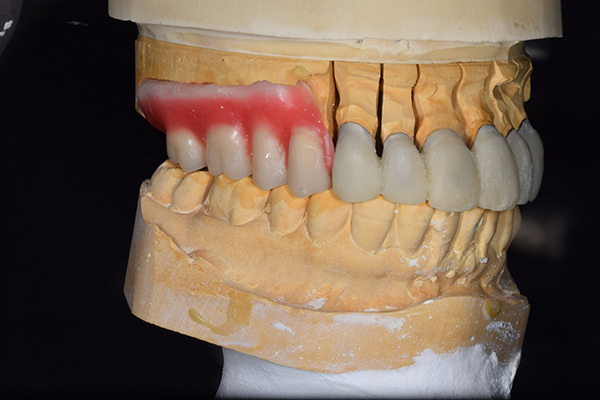

精密な型取りの後、噛み合わせのチェックをしていきました。 かぶせ物も同時に作っていきました。

歯を並べた後、かぶせ物のフレーム作ってもらいました。先に歯を並べて理想の位置を決めておくことが大切です。

噛み合わせチェックでしっかり奥歯で噛めるようにし、 歯を並べます。 その後、それに合わせて前歯を作っていきます。

最終的な入れ歯用の型取りをします。 シリコンで精密に型取りができました。

こちらが完成したかぶせ物と入れ歯です。かぶせ物にはアタッチメントをつけて金属のバネが見えない構造になっています。 入れ歯自体も金属を使用して、極力違和感がでないように、薄く作成しました。